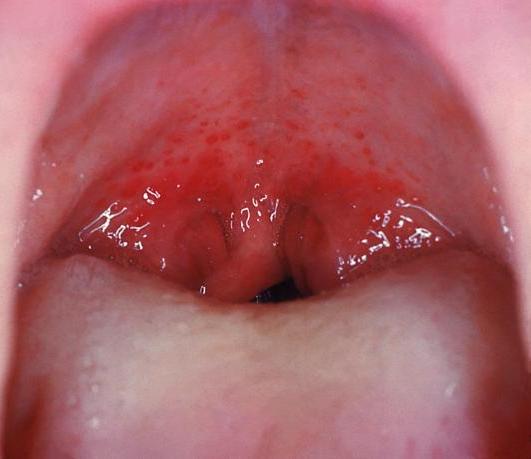

연구개 점상출혈은 주로 연쇄상구균 인두염과 관련이 있으며[6], 드물지만 매우 특이적인 소견이다.[7] 연구개 점상출혈 사례의 10~30%는 습관적이거나 구강 성교로 인해 발생하는 것으로 추정된다.[8]